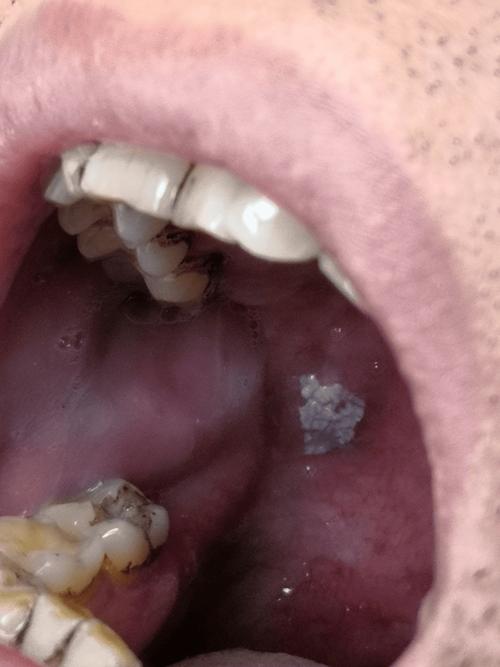

口腔粘膜白斑是指发生在口腔粘膜上的,以白色为主的斑块或斑片,不能被擦掉,也不能诊断为其他任何疾病(如念珠菌感染、白斑病等),它是一种癌前病变,意味着它有转变为口腔鳞状细胞癌的风险。

(图片来源网络,侵删)- 摩擦性/创伤性白斑:这是最常见的一种,如果白斑的形成是由于尖锐的牙齿边缘、不良修复体(如假牙)、过烫的食物或长期吸烟等物理化学刺激引起的,那么一旦去除这些刺激因素,部分白斑是有可能逐渐变淡甚至消失的,如果你是因为牙齿太尖刮破了口腔,医生磨平牙齿后,白斑就可能自愈。

- 如果白斑的形成与烟草、酒精等长期刺激有关,或者本身就是非均质型白斑(表面出现皱纹、硬结、糜烂、溃疡,甚至呈疣状或颗粒状),那么自愈的可能性就非常小。